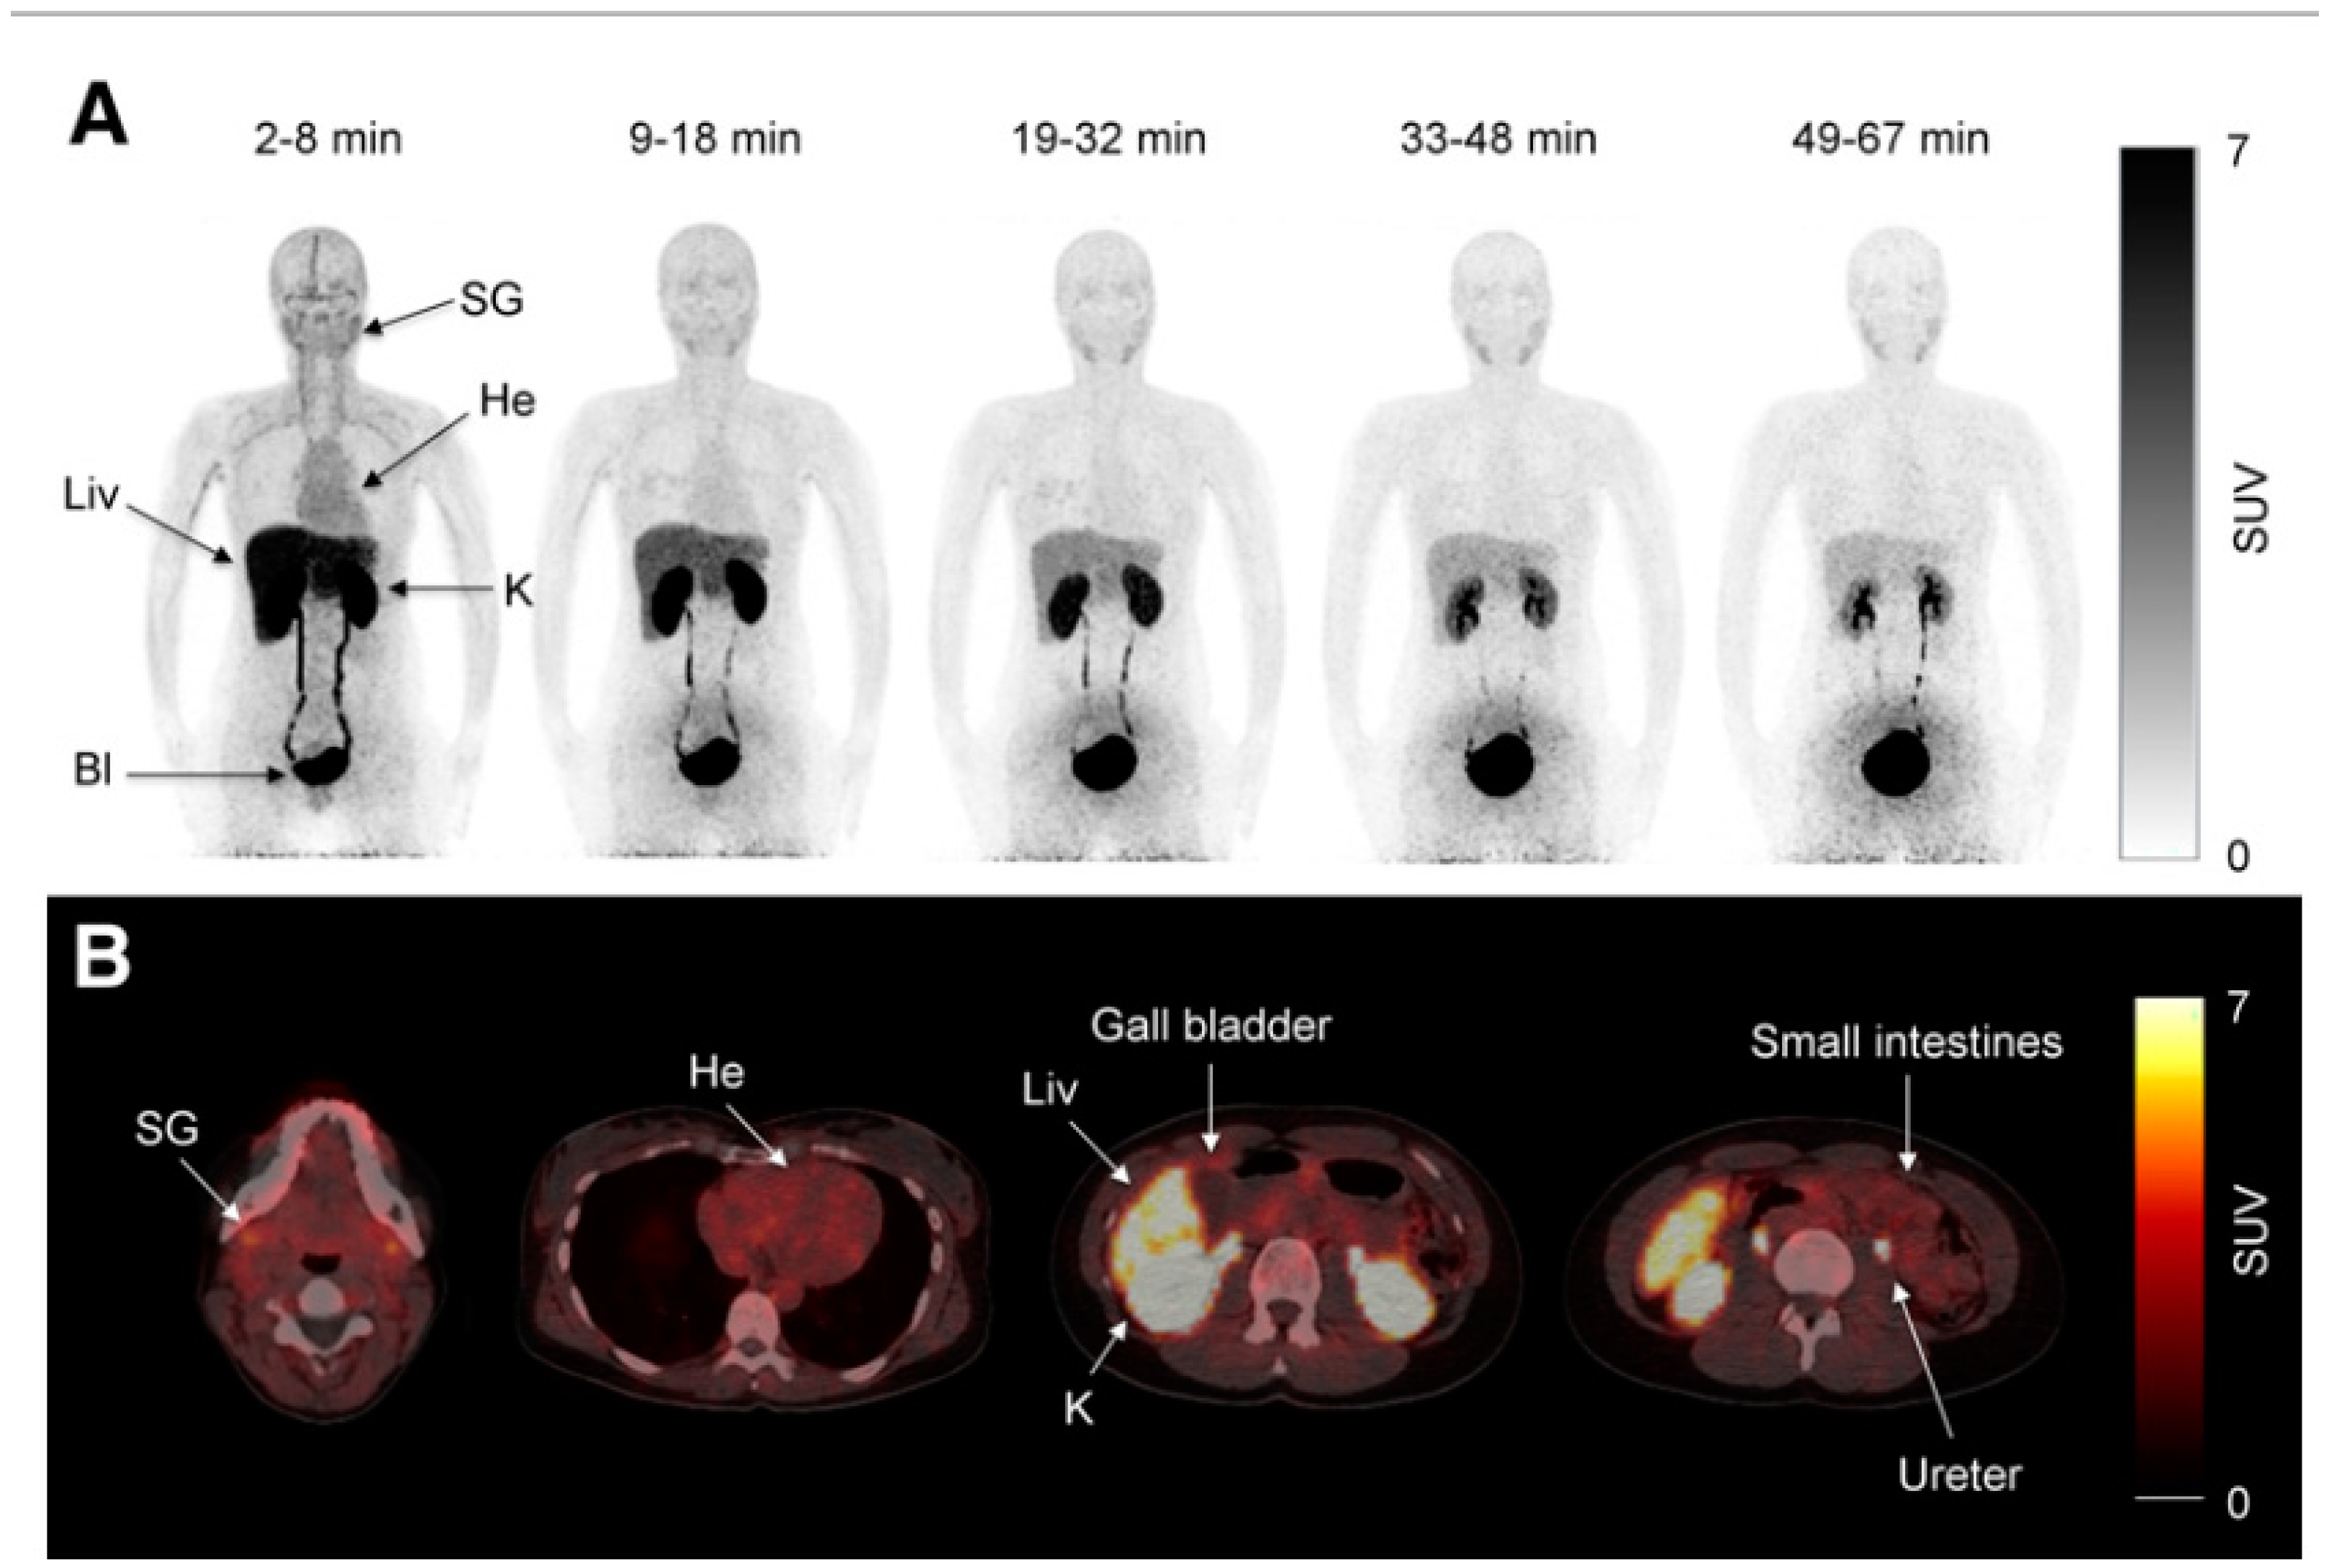

Morita and coworkers by using positron emission tomography (PET)-MRI, recently found that the maximum standardized uptake value (SUVmax) of F18-FDG in the intestine (jejunum,ileum and right or left hemicolon) of metformin treated diabetics was higher than that of the control group.More importantly the study permitted to differentiate the SUVmax of the intestinal wall from that of the intestinal lumen.The SUVmax of the intraluminal space in metformin-treated diabetics was greater than that of controls (Figure 2).On the contrary the SUVmax of the intestinal wall was similar in both groups (131).An increased accumulation of the injected tracer seems to be appreciable (Figure 3) also in the liver of metformin-treated diabetics up to 48 hours after interruption of the oral uptake of the drug (132,133).

Figure 2. PET-images taken 60 minutes after intravenuous administration of F18-FDG in a diabetic patient treated with metformin (A) and in a control patient(B).In A radiactivity has accumulated in the last portion of the ileum and in the colon (right hemicolon stronger than left hemicolon).The indication for the study was gall bladder cancer as confirmed by the accumulation oft he tracer in the gall bladder(arrow).From Morita Y et al.(131).